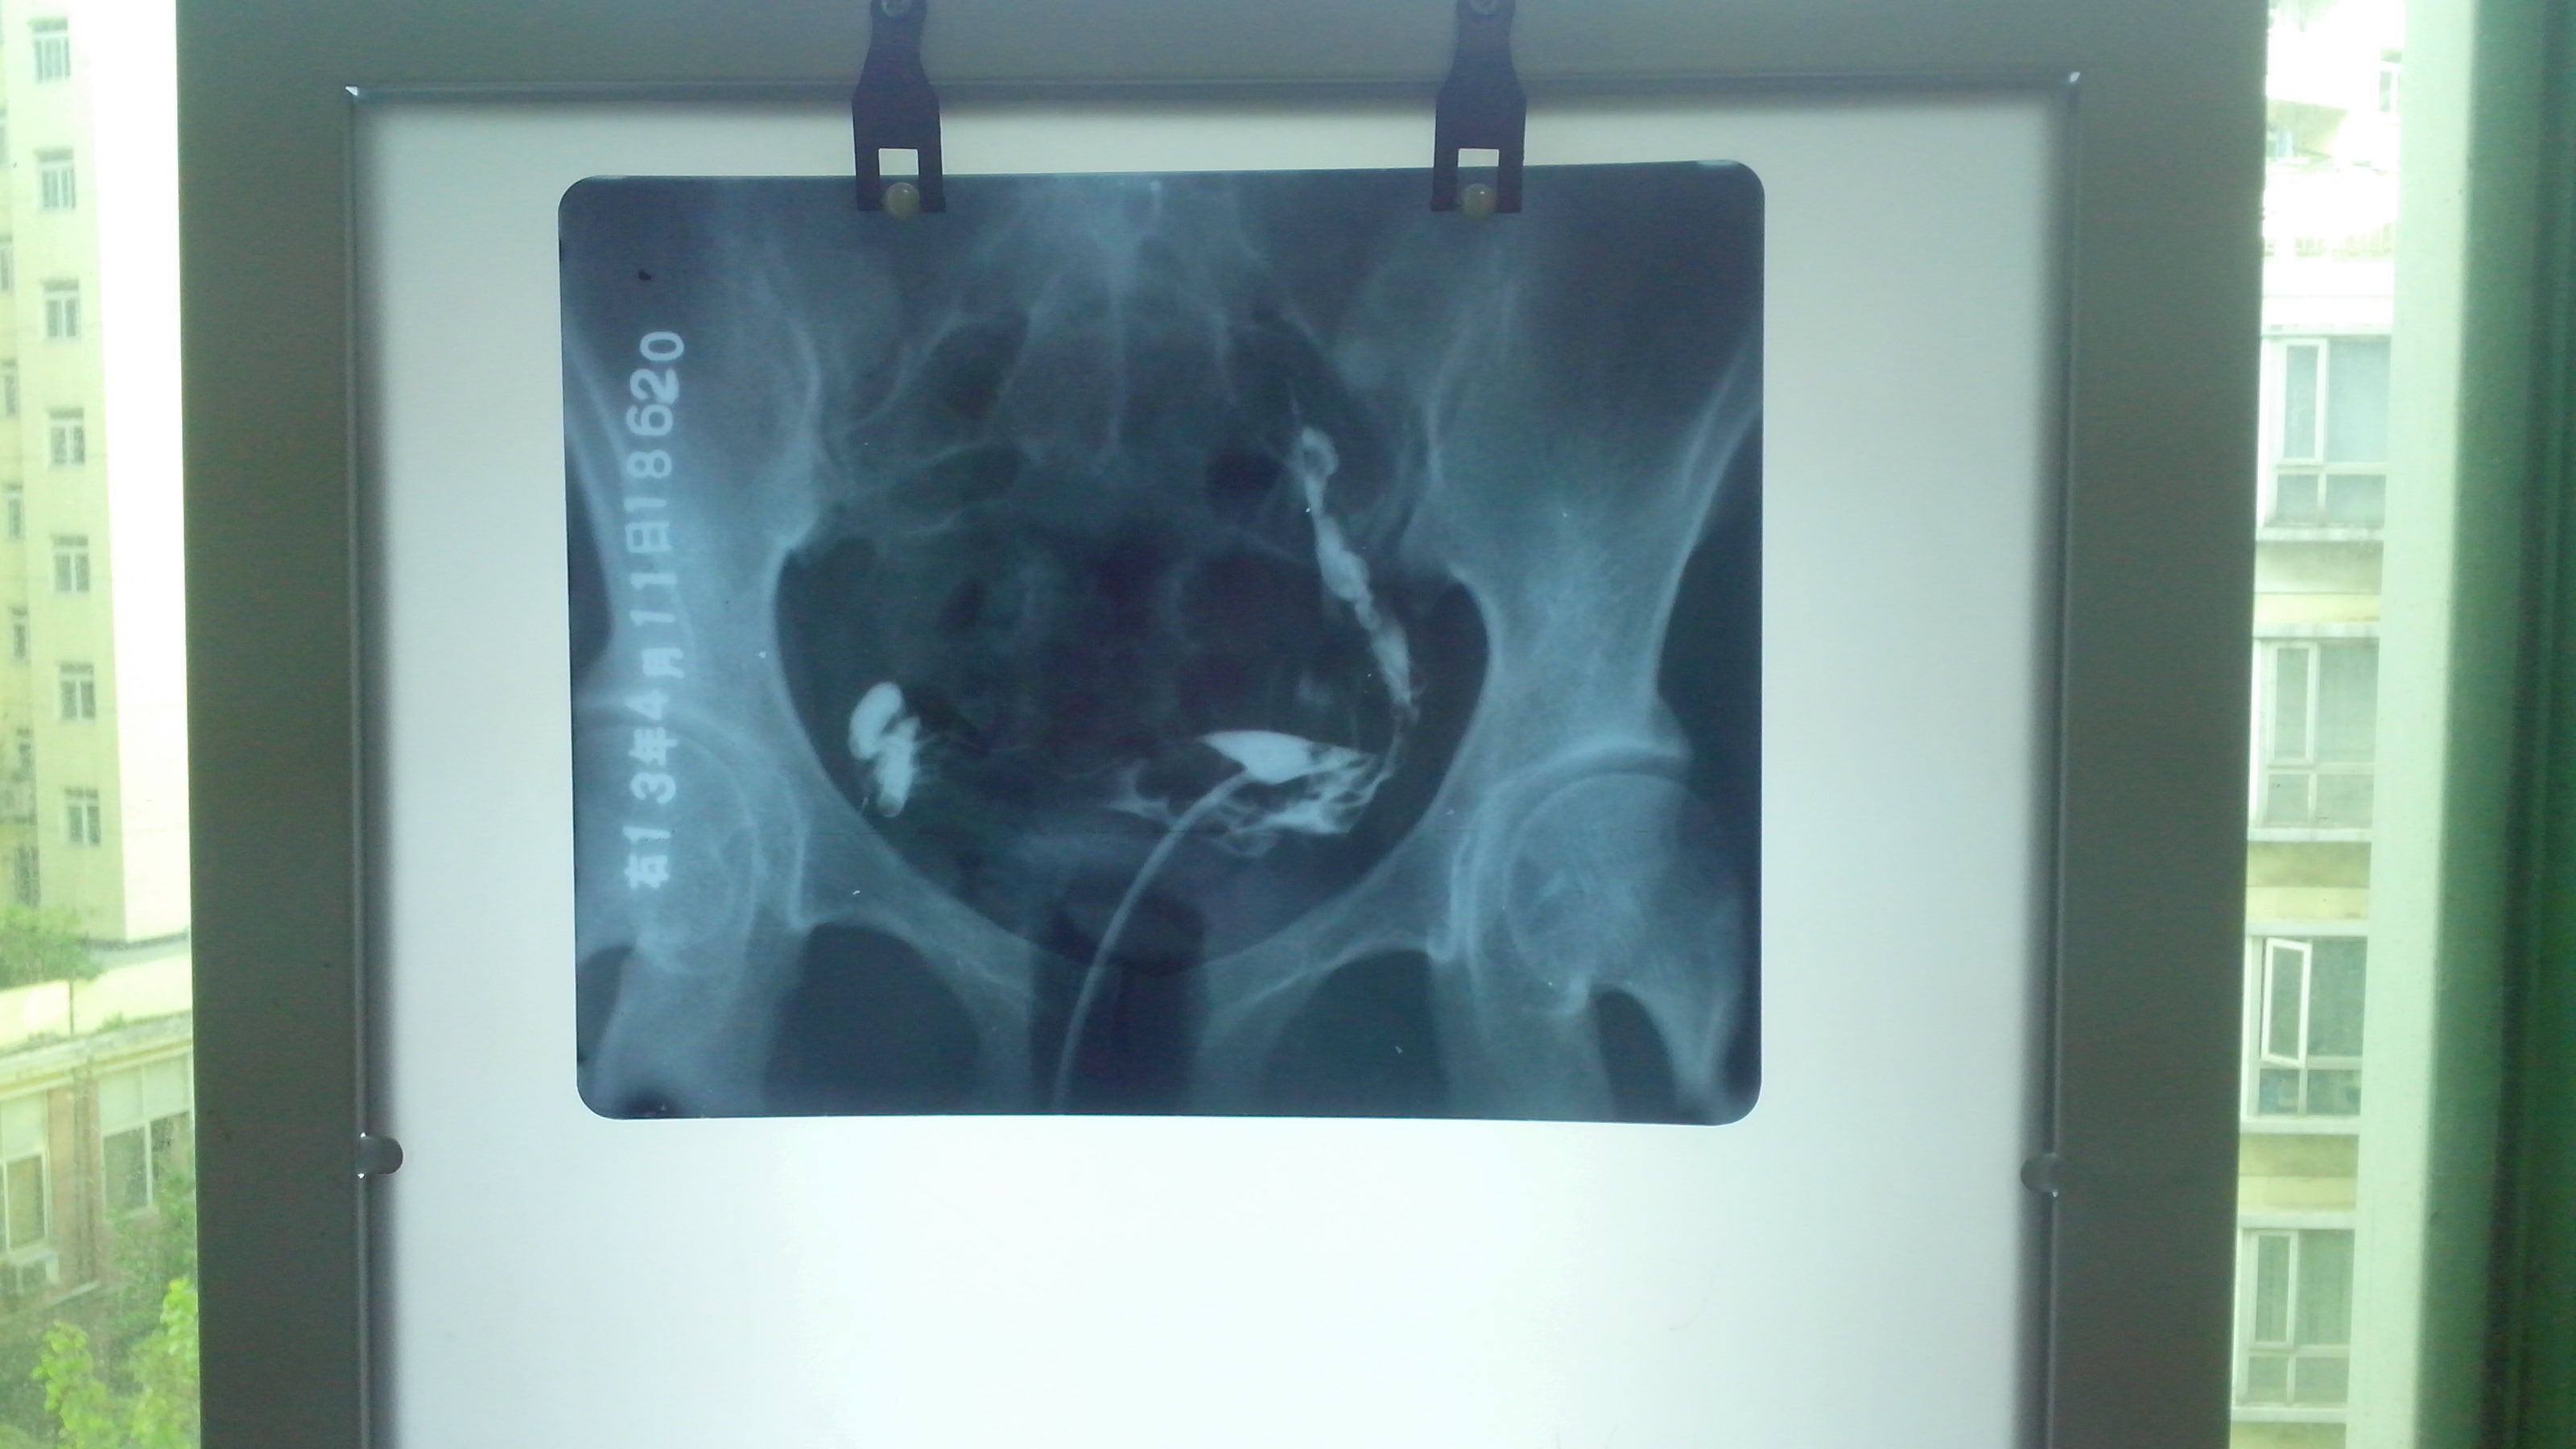

9年前宫外孕做了保留输卵管手术,今年检查,医生说右侧输卵管伞端积水,左则输卵管上举,不想手术怎么办 这是造影报告,能否用自身调理恢复,不想手术 点击展开 匿名用户 2013-05-15 22:34 满意回答 左侧是可以不手术的,但是右侧最好手安缘术治疗,如果没有生育要评葛求,也无明显不适症状的话,可以继续观了筛贸察。 匿名用户 2013-05-15 23:22 宝宝知道提示您:回答为网友贡献,仅供参考。 相关问题 宫外孕开刀手术保留输卵管,发现右侧输卵管右积水,已处理我怀孕机率有多大? 有没有宝妈和我一样五周去做B超,显示宫内没胎儿,而输卵管间歇处长了个不知是什么,医生也不确定宫外孕 怀孕初期,喝鲫鱼汤能治输卵管积水吗?防止宫外孕吗?